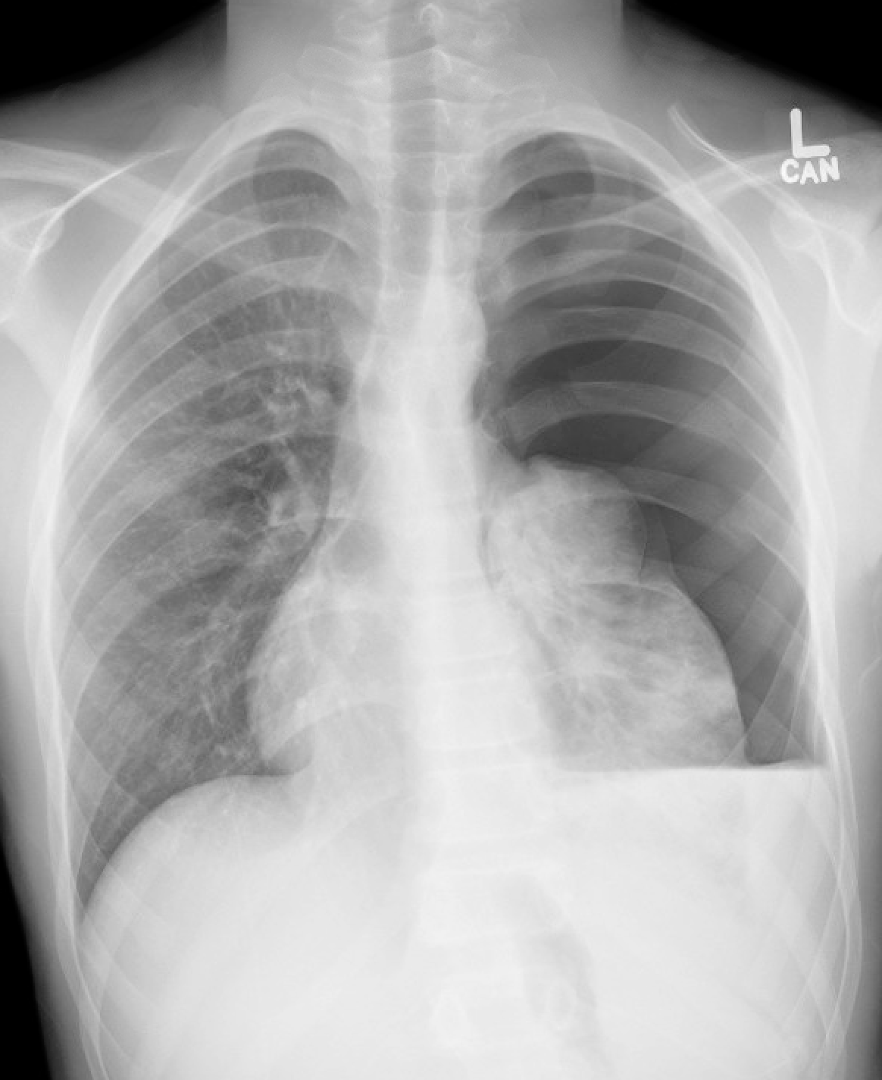

Case: A helmeted 13-yo-boy carrying a friend on his e-scooter ran into a pole and was pinned against the handle. He was brought in by his parents for chest pain from periphery to SMH. His CXR shows rib fractures and a tension hemopneumothorax. He is hypoxic and requires a decompression. What is the ideal location for needle decompression according to 2025 ATLS?

Discussion: 2025 ATLS recommends 2nd ICS at midclavicular line in peds and 4th/5th ICS anterior to midaxillary line in adults. Transition from peds to adult for placement site is considered based on chest wall thickness and patient size (around age 13). See latest EB article for a deeper dive.